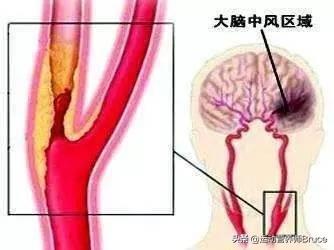

血管狭窄を引き起こし、最も深刻なプラークは、心血管プラーク、または頸動脈プラークであり、これらのプラークの悪化は、心筋虚血、脳虚血につながる;積極的に制御しない場合、あるいはプラークの血栓症の破裂が発生し、心筋梗塞、脳梗塞をもたらす。

高脂血症などの心血管危険因子の影響により、血管の内壁は徐々に傷つき、血液中の余分な脂質は徐々に血管壁の下に沈着し、黄色い粥腫性脂質コアを形成し、最終的には脂質コアに線維性被膜が形成され、これが動脈プラークの形成過程である。 プラークは動脈硬化を引き起こす危険因子であり、安定性や破裂に問題のあるプラークは、反応性血小板血小板の反応性凝集は血栓を形成し、動脈血管を閉塞させ、梗塞性心血管病を引き起こすことさえある。したがって、私たちはプラークの問題に注意を払う必要がありますが、通常、すでに形成されたプラークを元に戻したり除去したりすることは非常に困難であり、私たちがしなければならないことは、合理的な薬物療法と運動によってプラークの形成を予防し、既存のプラークに対して、プラークの安定性を維持するように努め、動脈硬化のプロセスを遅らせ、プラークの破裂がより大きなリスクを引き起こすのを防ぐことです。

プラークは、静脈プラーク、動脈プラークを持って、それは複数の病因因子の役割にある、沈殿物の脂質化のために、単刀直入に言えば、つまり、あなたがより多くのグリース、消化と使用することはできません、血中脂質4と他の多因子の影響下で、内膜に損傷を与え、血管の内層に沈着し、黄色のアテローム性脂質のコアの形成、および最終的に線維性キャップが持続的な炎症にさらされている場合、通常は非常に安定している脂質のコア、上の線維性コアの形成にある攻撃は、飲酒、怒り、夜更かし、少ない水を飲むなど、線維性キャップが破裂し、プラークが流出し、血液中の血小板が結婚フラッシュ、血栓と呼ばれるトラブルメーカーの子供を出産し、この子は、血管をブロックするために悪いことをすることに特化し、トラブルを作るためにさまよう、血管の内腔に血栓が同時に狭くなるだけでなく、破裂、急性心脳血管イベント、脳卒中、心筋梗塞、肺塞栓症、腎不全、静脈瘤などを誘発する。などである。したがって、プラークを除去することは、血管の詰まりを取り除くだけでなく、急性心血管系および脳血管系イベントを予防することにもなり、誰もが関心を寄せている。

動脈プラークは、複数の病因因子の影響下にある動脈内膜の損傷によって引き起こされる一連の炎症反応であり、後に二次的なアテローム性プラークが生成される。プラークの形成は人体にとってより有害であり、同時に血管の内腔を狭くし、破裂して急性心血管系イベントを誘発することもある。したがって、プラークを除去することは血管の詰まりを解消するだけでなく、急性心血管系イベントを予防することにもなり、これはすべての患者の心臓の鼓動である。プラークの治療には、血中脂質、血圧、血糖値などのコントロール、減塩、低コレステロール食、運動量の増加、禁煙、アルコール制限などの悪い生活習慣の改善など、病気の原因から始めるか、上記の治療の上に薬物療法を行うことができます。薬の選択は、アトルバスタチン、レセルプルバスタチンなどのスタチン系薬剤がアテローム性プラークの治療によく使用されます。具体的な治療計画は専門医の指導のもとに立てるべきである。

アテローム性動脈硬化症は、成人であれば思春期から誰もが経験する動脈血管の内皮病変である。数十年かけてゆっくりと進行し、最終的にはアテローム性動脈硬化斑を形成して血管を詰まらせたり、破裂させたりして、脳出血、脳梗塞、冠動脈疾患、大動脈瘤の分離などの重篤な心血管・脳血管疾患を引き起こす。